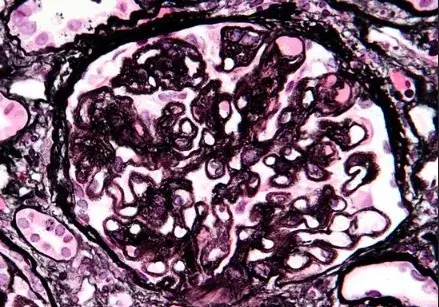

Nefropatia Membranosa: e se o paciente não responder ao tratamento inicial?

Neste vídeo, abordamos estratégias para lidar com pacientes com nefropatia membranosa que não respondem ao tratamento inicial. Ele enfatiza a importância da reavaliação constante e do ajuste do regime de tratamento com base nos resultados e no estado do paciente.

Como fazer o tratamento da Nefropatia Membranosa de forma prática!